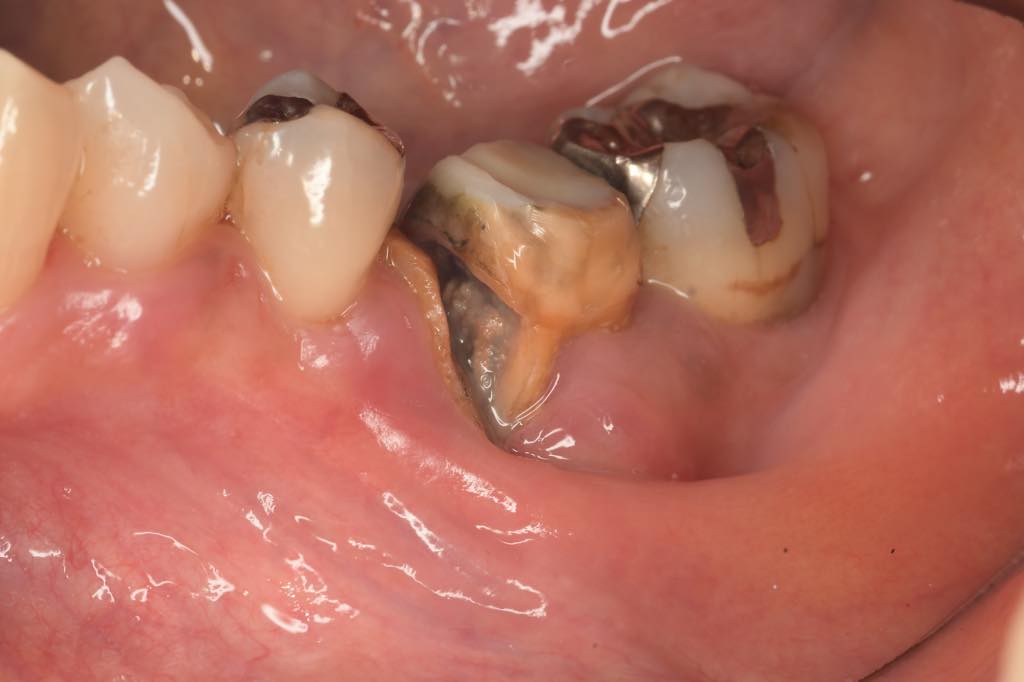

CASE 01

| 主訴 | 歯が割れた |

| 治療内容 | 左下6番 インプラント治療(骨の再生療法含む) |

| 治療回数 | 14回 |

| 治療費用 | ¥460,000 |

| 想定される副作用 | 腫れ、痛み |